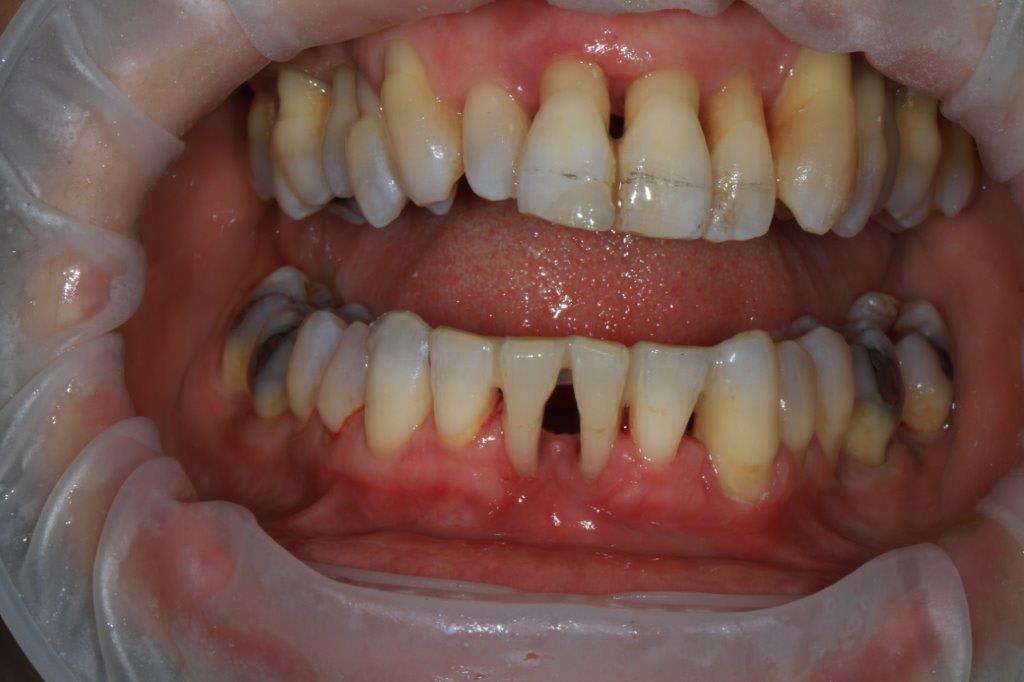

un peu de grain à moudre, toutes les critiques sont les bienvenues...

1ere séance,"nettoyage...", et après réflexion, plutôt que le nettoyage par le vide, attelle de contention pour le bloc antérieur mandibulaire, suppression de quelques contact très parasite sur les pm et canines, et réduction des incisives mandibulaire puis maxillaire... consignes de brossages / bain de bouche avec .... l'érythritol afin de ne pas mourir idiot... on verra ce que ça donne dans un cas relativement perdu d'avance.... merci Algi... enfin peut être : -))

C est dommage que l'on ne voit pas les dents en occlusion .

La 12 est en occlusion inverse et le secteur postérieur 20/30 aussi ?

Une fois de plus ce n est pas un pb Paro mais bien occlusal .

effectivement, je vois la conséquence paro d'un problème avec départ occlusal, mais peut être pas que.